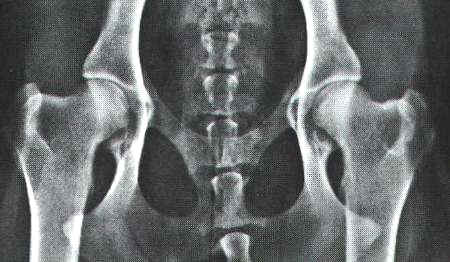

schwere HD - Aufnahme bei einem Schäferhund |